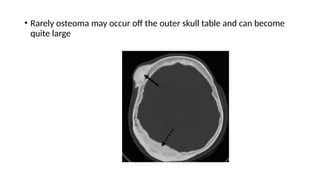

• Rarely osteoma may occur off the outer skull table and can become

quite large

Radiological features • Roundor oval radio-opaque structure < 2 cm. • In case of giant osteoma , expansion of sinus wall can happen

• Rarely osteomamay occur off the outer skull table and can become quite large